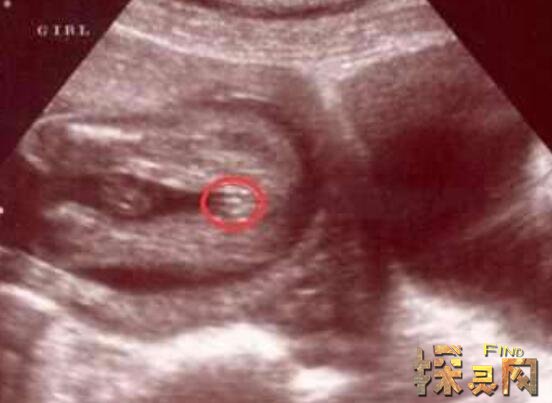

1、B超

在医院做B超是最容易看出是男孩还是女孩,它主要是通过超声波扫描,在图像上显示男孩和女孩决然不同生殖器官,不过也不排除看不清楚情况。一般来说,超声波在检测胎儿性别时候,男婴正确率要高于女婴的,当然也有一定检测误差。